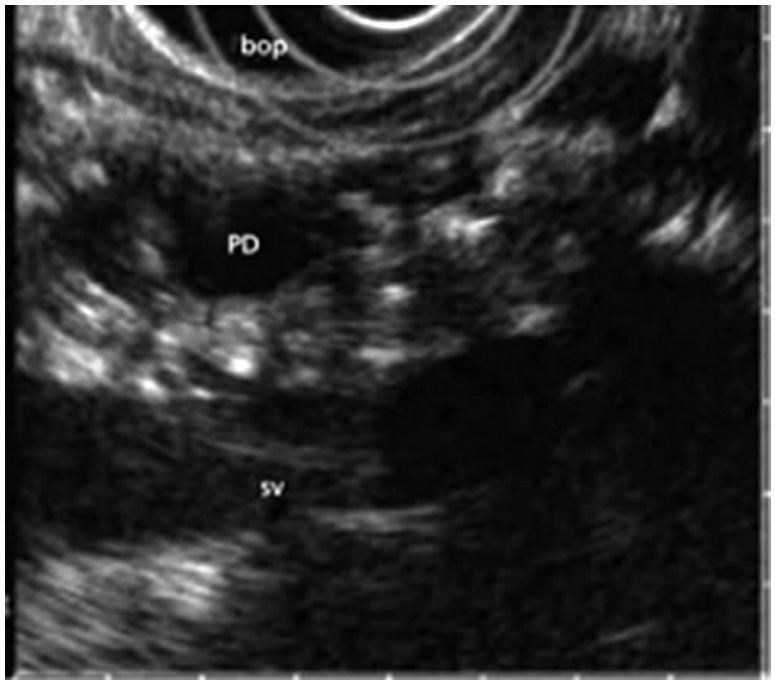

超声内镜(Endoscopic Ultrasound,EUS)是将内镜和超声相结合的消化道检查技术:将微型高频超声探头安置在内镜顶端,当内镜插入消化道后,在内镜直接观察消化道病变的同时,利用内镜下的超声实时扫描消化道及周围结构。

相比于常规的腹部B超,超声内镜技术探查胰腺具有天然的优势。因利用消化道自然腔道进行探查(胃壁紧邻胰腺),可有效避开腹壁脂肪、胃肠道气体等的干扰,而且能了解病变深度、起源,此外,还可通过穿刺、引流、注射及粒子种植等方法进行相关治疗。

超声内镜对于胰腺先天性发育异常的诊断准确率明显高于常规影像手段(95%以上),弥补了对于胰腺发育异常缺乏诊断工具的缺憾,并通过进一步胰管支架或胰管引流,有效缓解急性胰腺炎,避免再发;